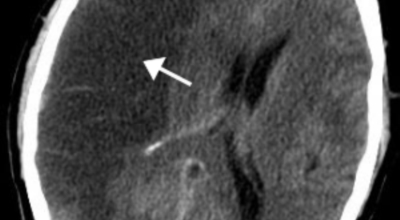

뇌졸중은 뇌경색과 뇌출혈 두가지로 나뉘게 돼요. 먼저 뇌경색은 뇌혈관이 막혀 영양분과 산소를 주는 피가 통하지 않는 상태로 원은은 크게 세 가지로 나눌 수 있는데요 동맥경화증이 생겨 좁아진 부위로 인하여 혈액공급이 부족해지거나 좁아지다가 결국 막혀버리는 경우, 큰 혈관에서 분지한 작은 혈관들이 고혈압 등으로 압박을 받으면 혈관이 막히는 경우가 있습니다.

또한 심장 판막질환이나 심방세동 또는 심근병 등등의 심장 질환이 있는 경우 심장에서 혈전이 만들어지고 그게 뇌로 흘러가게 되면 뇌혈관을 막게 되는 경우가 있답니다. 뇌출혈은 뇌경색과 반대로 뇌혈관이 터져서 생기는 뇌내 출혈과 거미막하 출혈로 나누게 돼요. 거미막하출혈은 혈관벽의 약한 부분이 부풀어 오르는 뇌동맥류가 터지는 경우와 관련성이 크다고 해요.